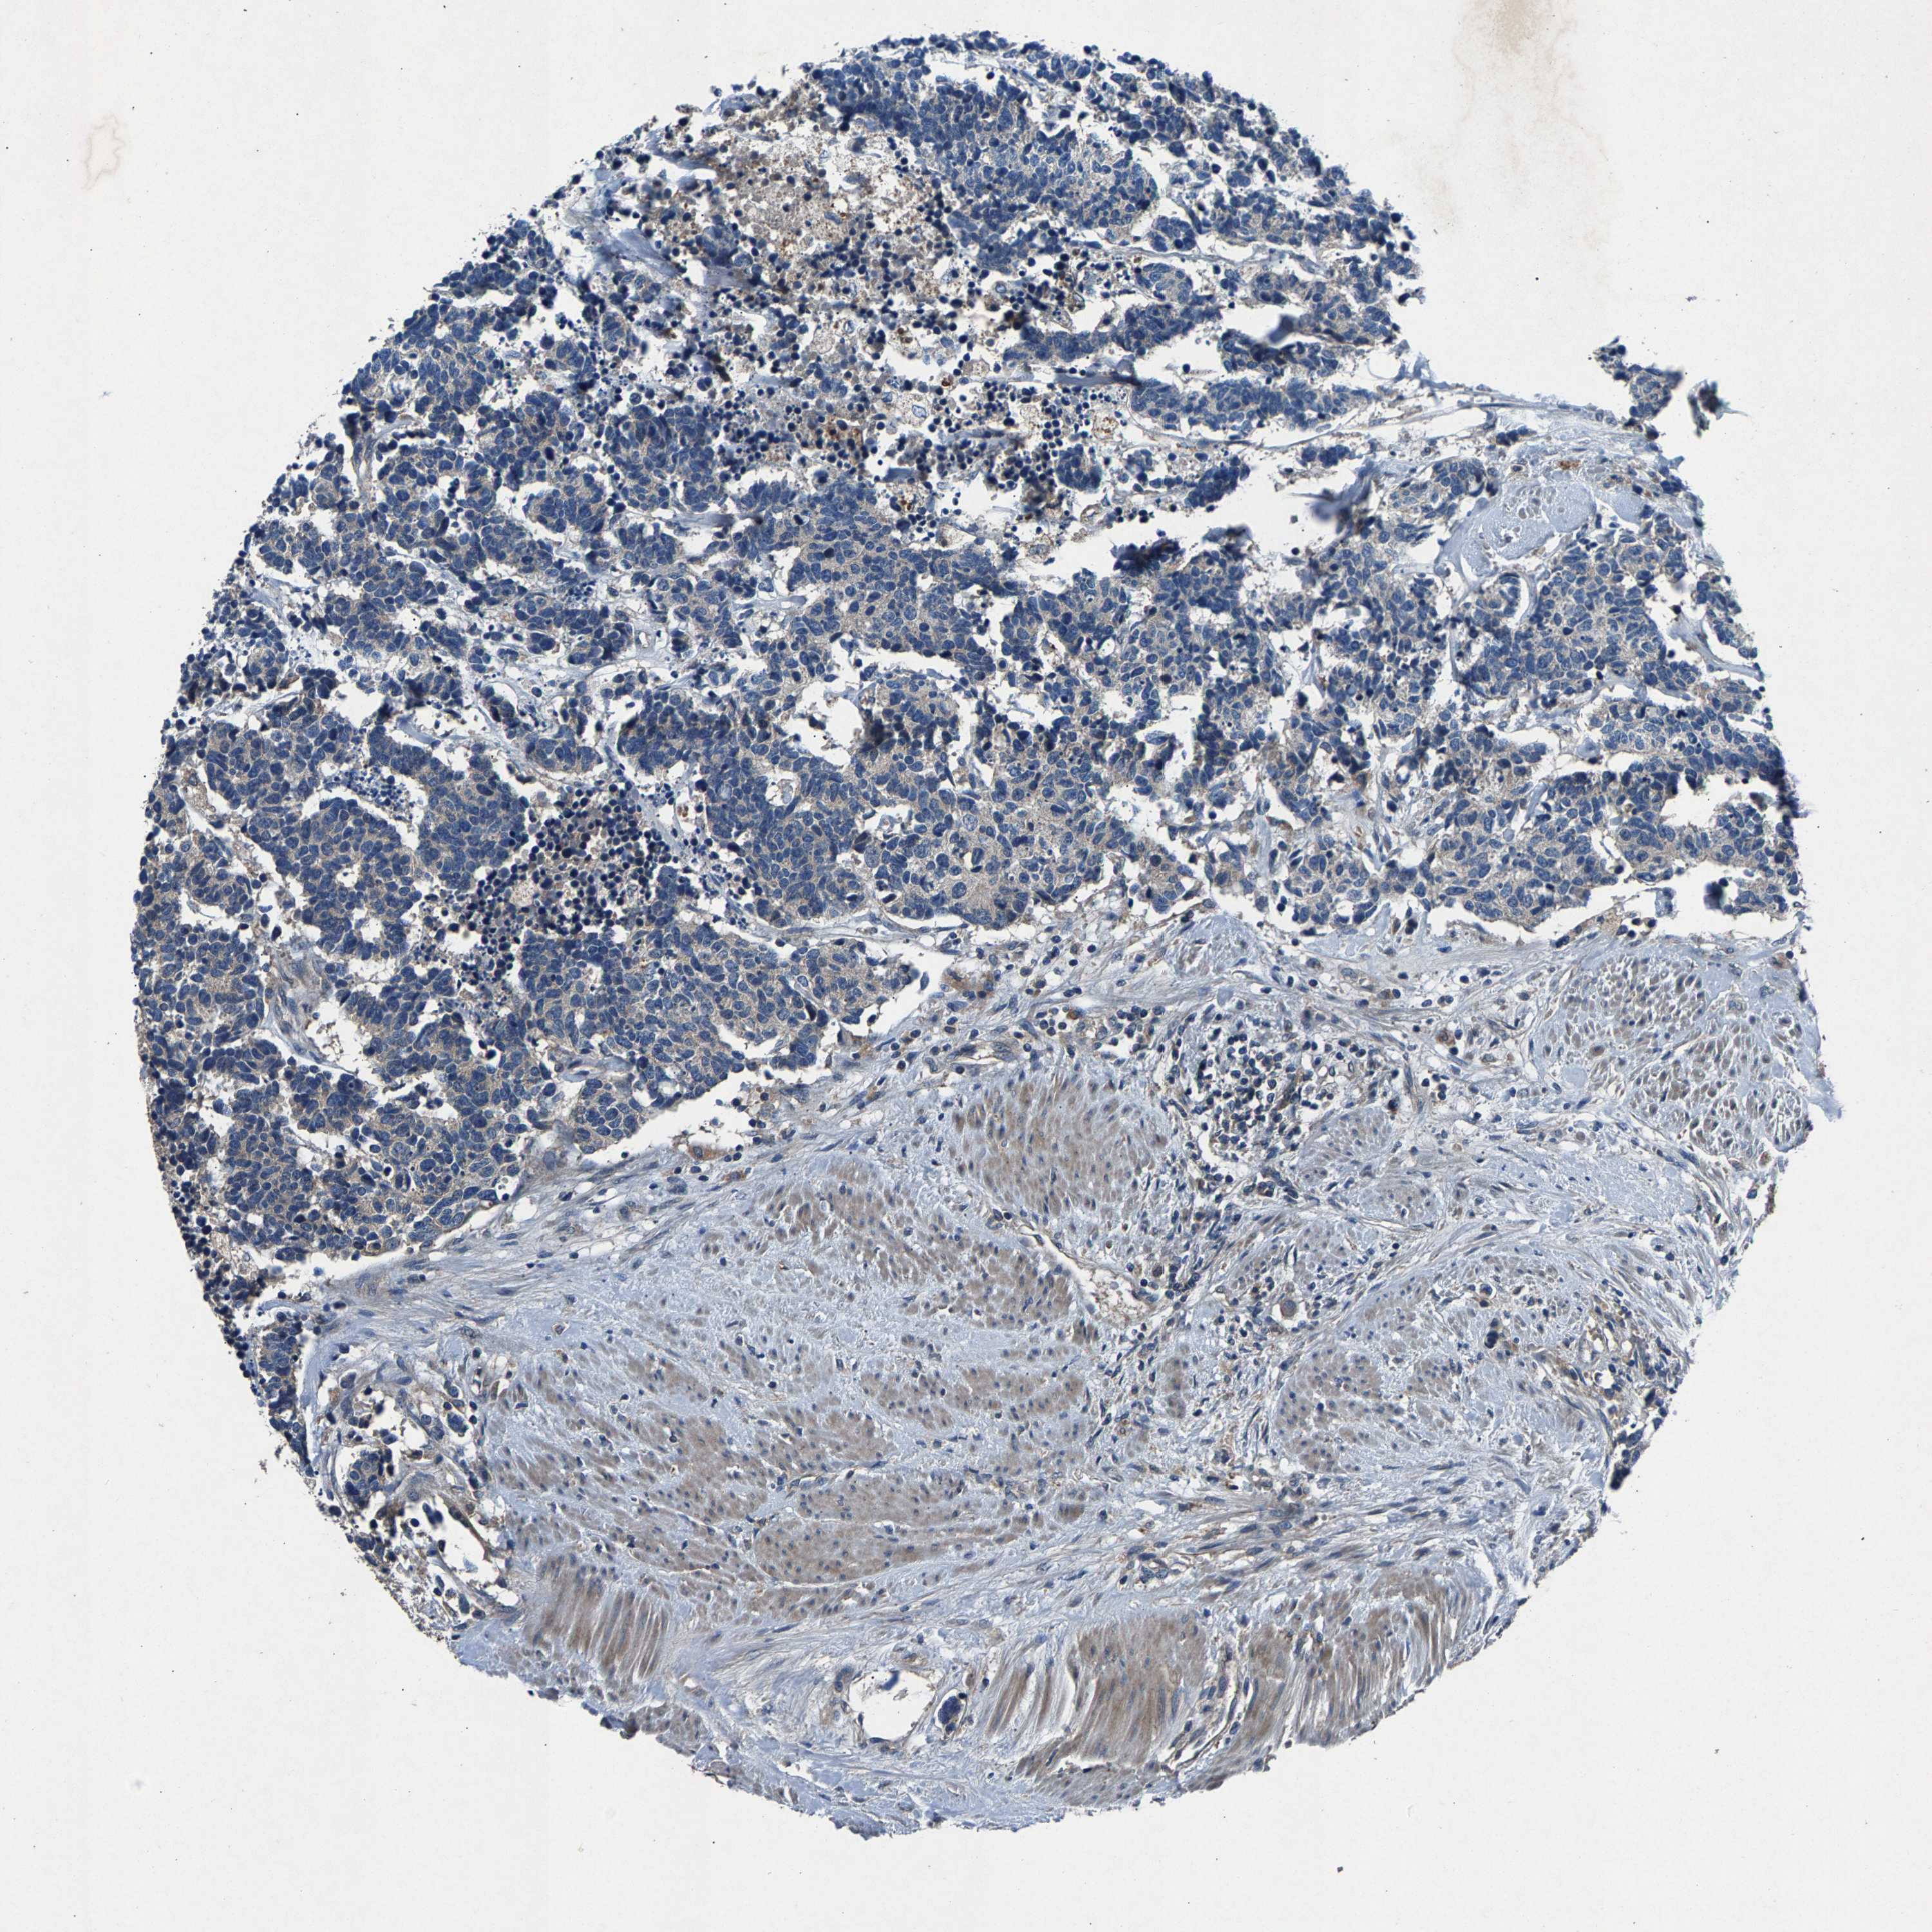

CARCINOID - Protein expressioni

A mouse-over function shows sample information and annotation data. Click on an image to view it in a full screen mode. Samples can be filtered based on level of antibody staining by selecting one or several of the following categories: high, medium, low and not detected. The assay and annotation is described here.

Antibody stainingi

Antibody staining in the annotated cell types in the current human tissue is reported as not detected, low, medium, or high, based on conventional immunohistochemistry profiling in selected tissues. This score is based on the combination of the staining intensity and fraction of stained cells.

Each image is clickable and will lead to virtual microscopy that enables deeper exploration of all samples and also displays staining intensity scores, fraction scores and subcellular localization as well as patient and tissue information for each sample.

Antibody HPA021294

Staining

High

Medium

Low

Not detected

Intensity

Strong

Moderate

Weak

Negative

Quantity

>75%

75%-25%

<25%

None

Location

Nuclear

Cytoplasmic/membranous

Cytoplasmic/membranous,nuclear

Carcinoid, malignant, NOS

Carcinoma, NOS